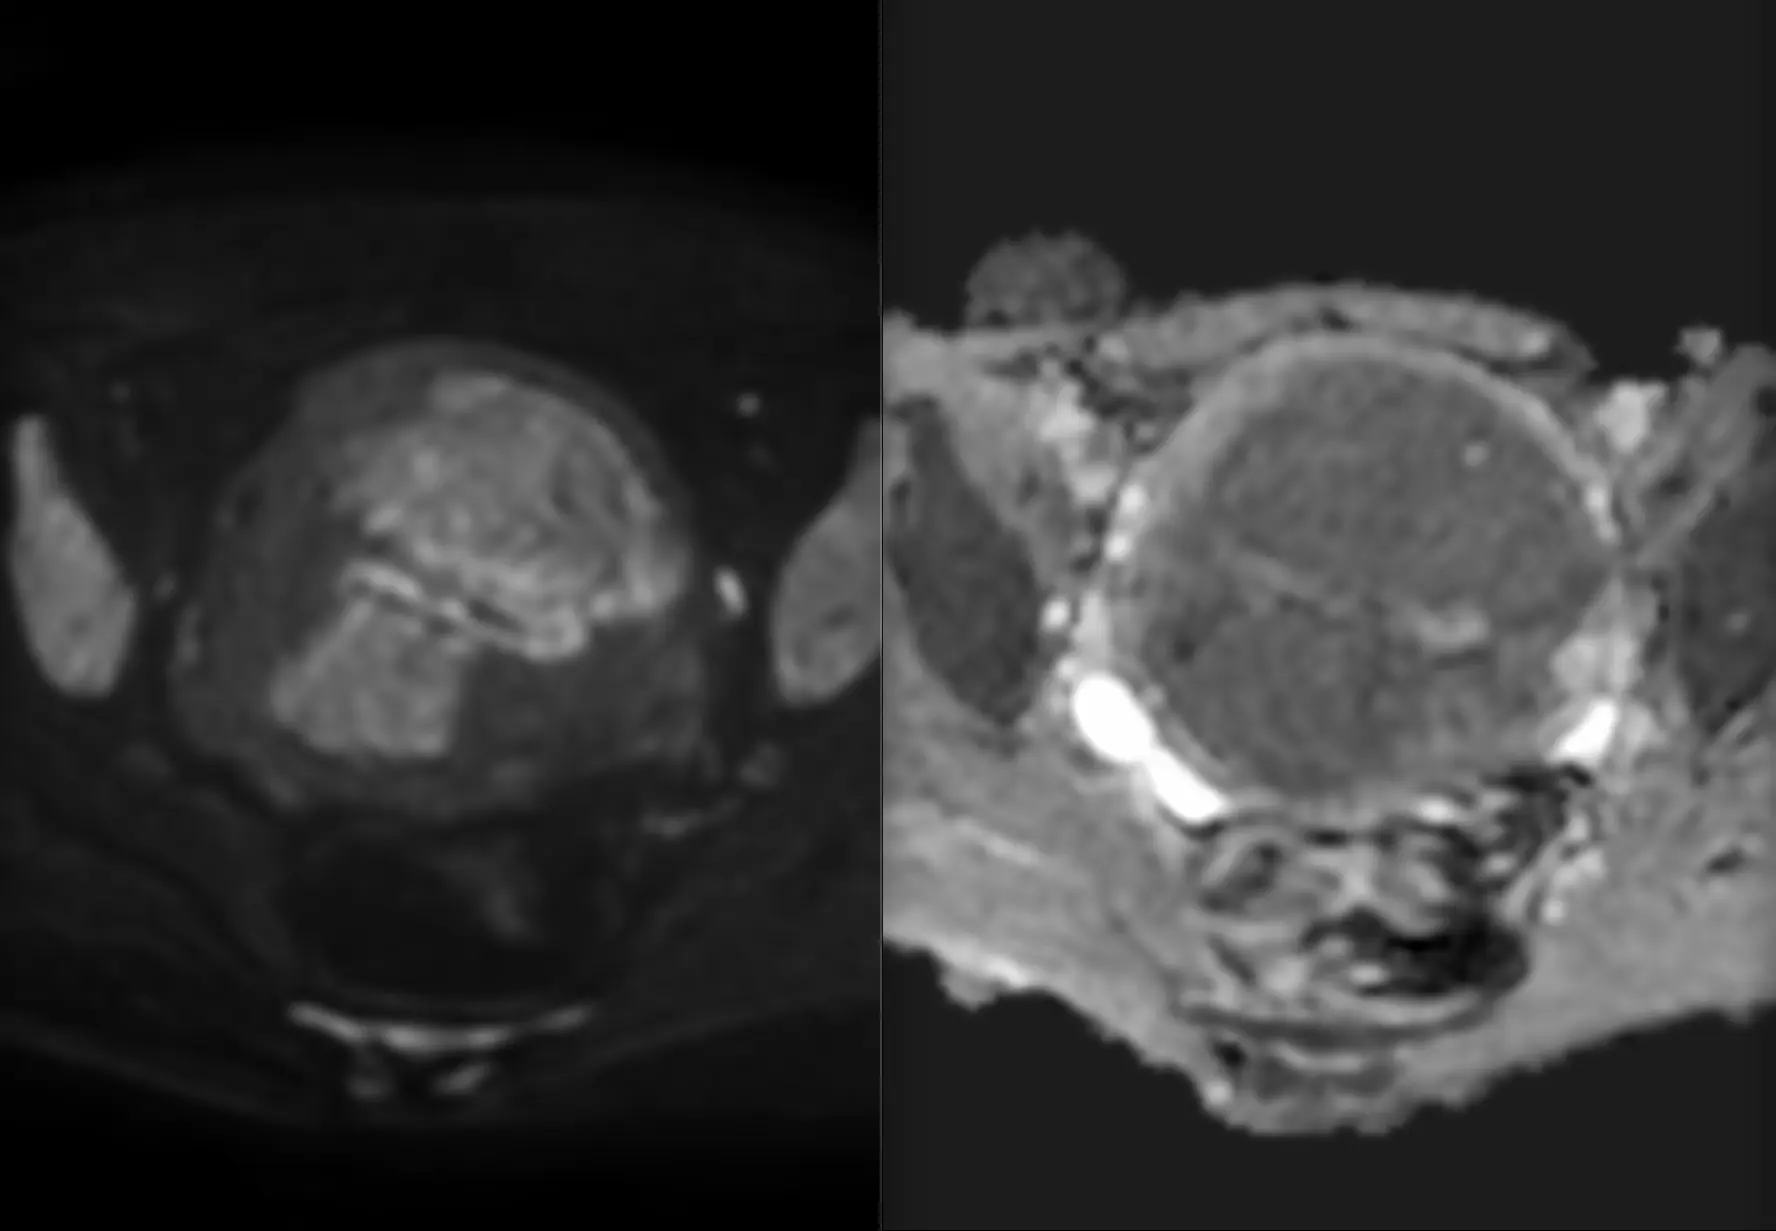

Сделали мочевой пузырь с контрастом, оказалось три образования в стенке, категория по ви-рац – четвёрка.

То, что по КТ выглядело, как огромное образование, по большей части оказалось кровяным сгустком. Оценить стенку на мрт с контрастом оказалось возможным только благодаря вычитанию, рекомендуем это всем, кто занимается оценкой стадий рака мочевого пузыря на МРТ. Помогает, когда внутри сгустки крови, яркие на нативной T1W.

Вот и думай теперь, что с этим делать. Пузырь удалять?